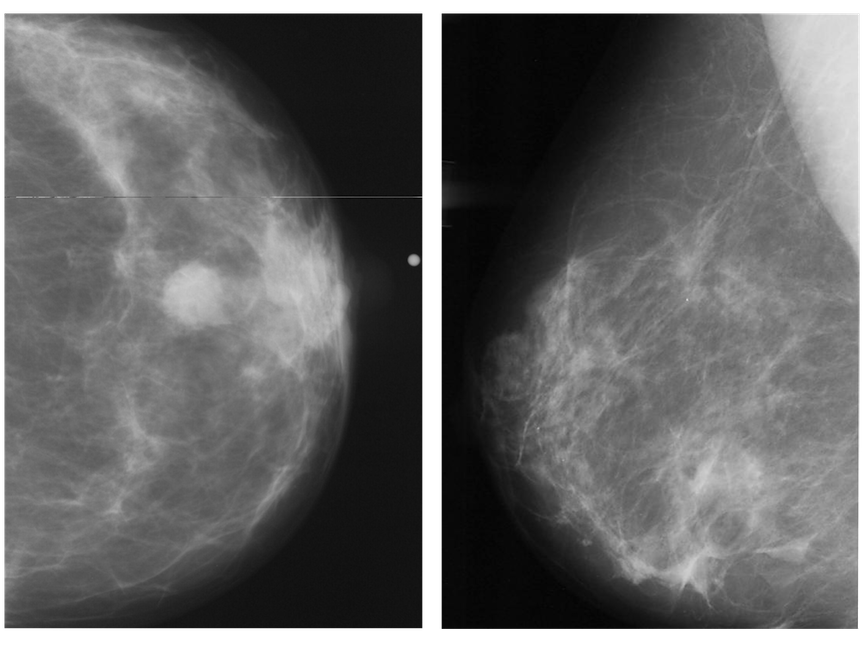

Three areas in medicine have such a framework for quality assurance: mammography, surgery, and blood bank pathology. Facilities offering mammography must abide by the U.S. Food and Drug Administration’s (FDA) Mammography Quality Standards Act. Group practices and radiologists in breast imaging also have a wealth of data on their own performance and they have a closed system with repeat patients, Rubio said.